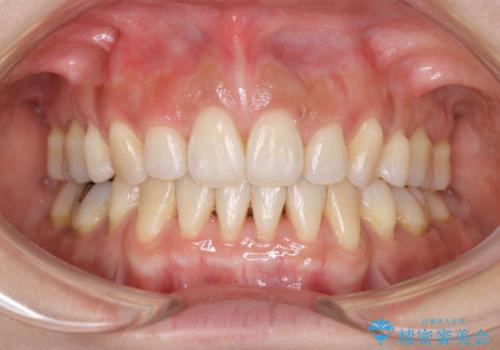

- 出っ歯がきになるとのことで来院されました。

上顎の前歯は前方に傾斜しており、下あごの前歯にもガタガタがありました。

上下左右の小臼歯を合計4本抜歯して矯正することとしました。

矯正を開始する前から歯肉退縮があり、悪化しないように注意しながら矯正治療を行いました。